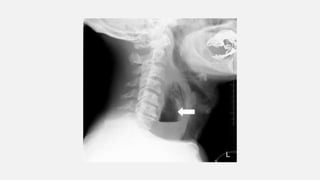

XRAY

NECK:NARROWING

OF THE SUBGLOTTIC

REGION “STEEPLE

SIGN”

Xray soft tissue neck

lateral view :

Thumbprint sign